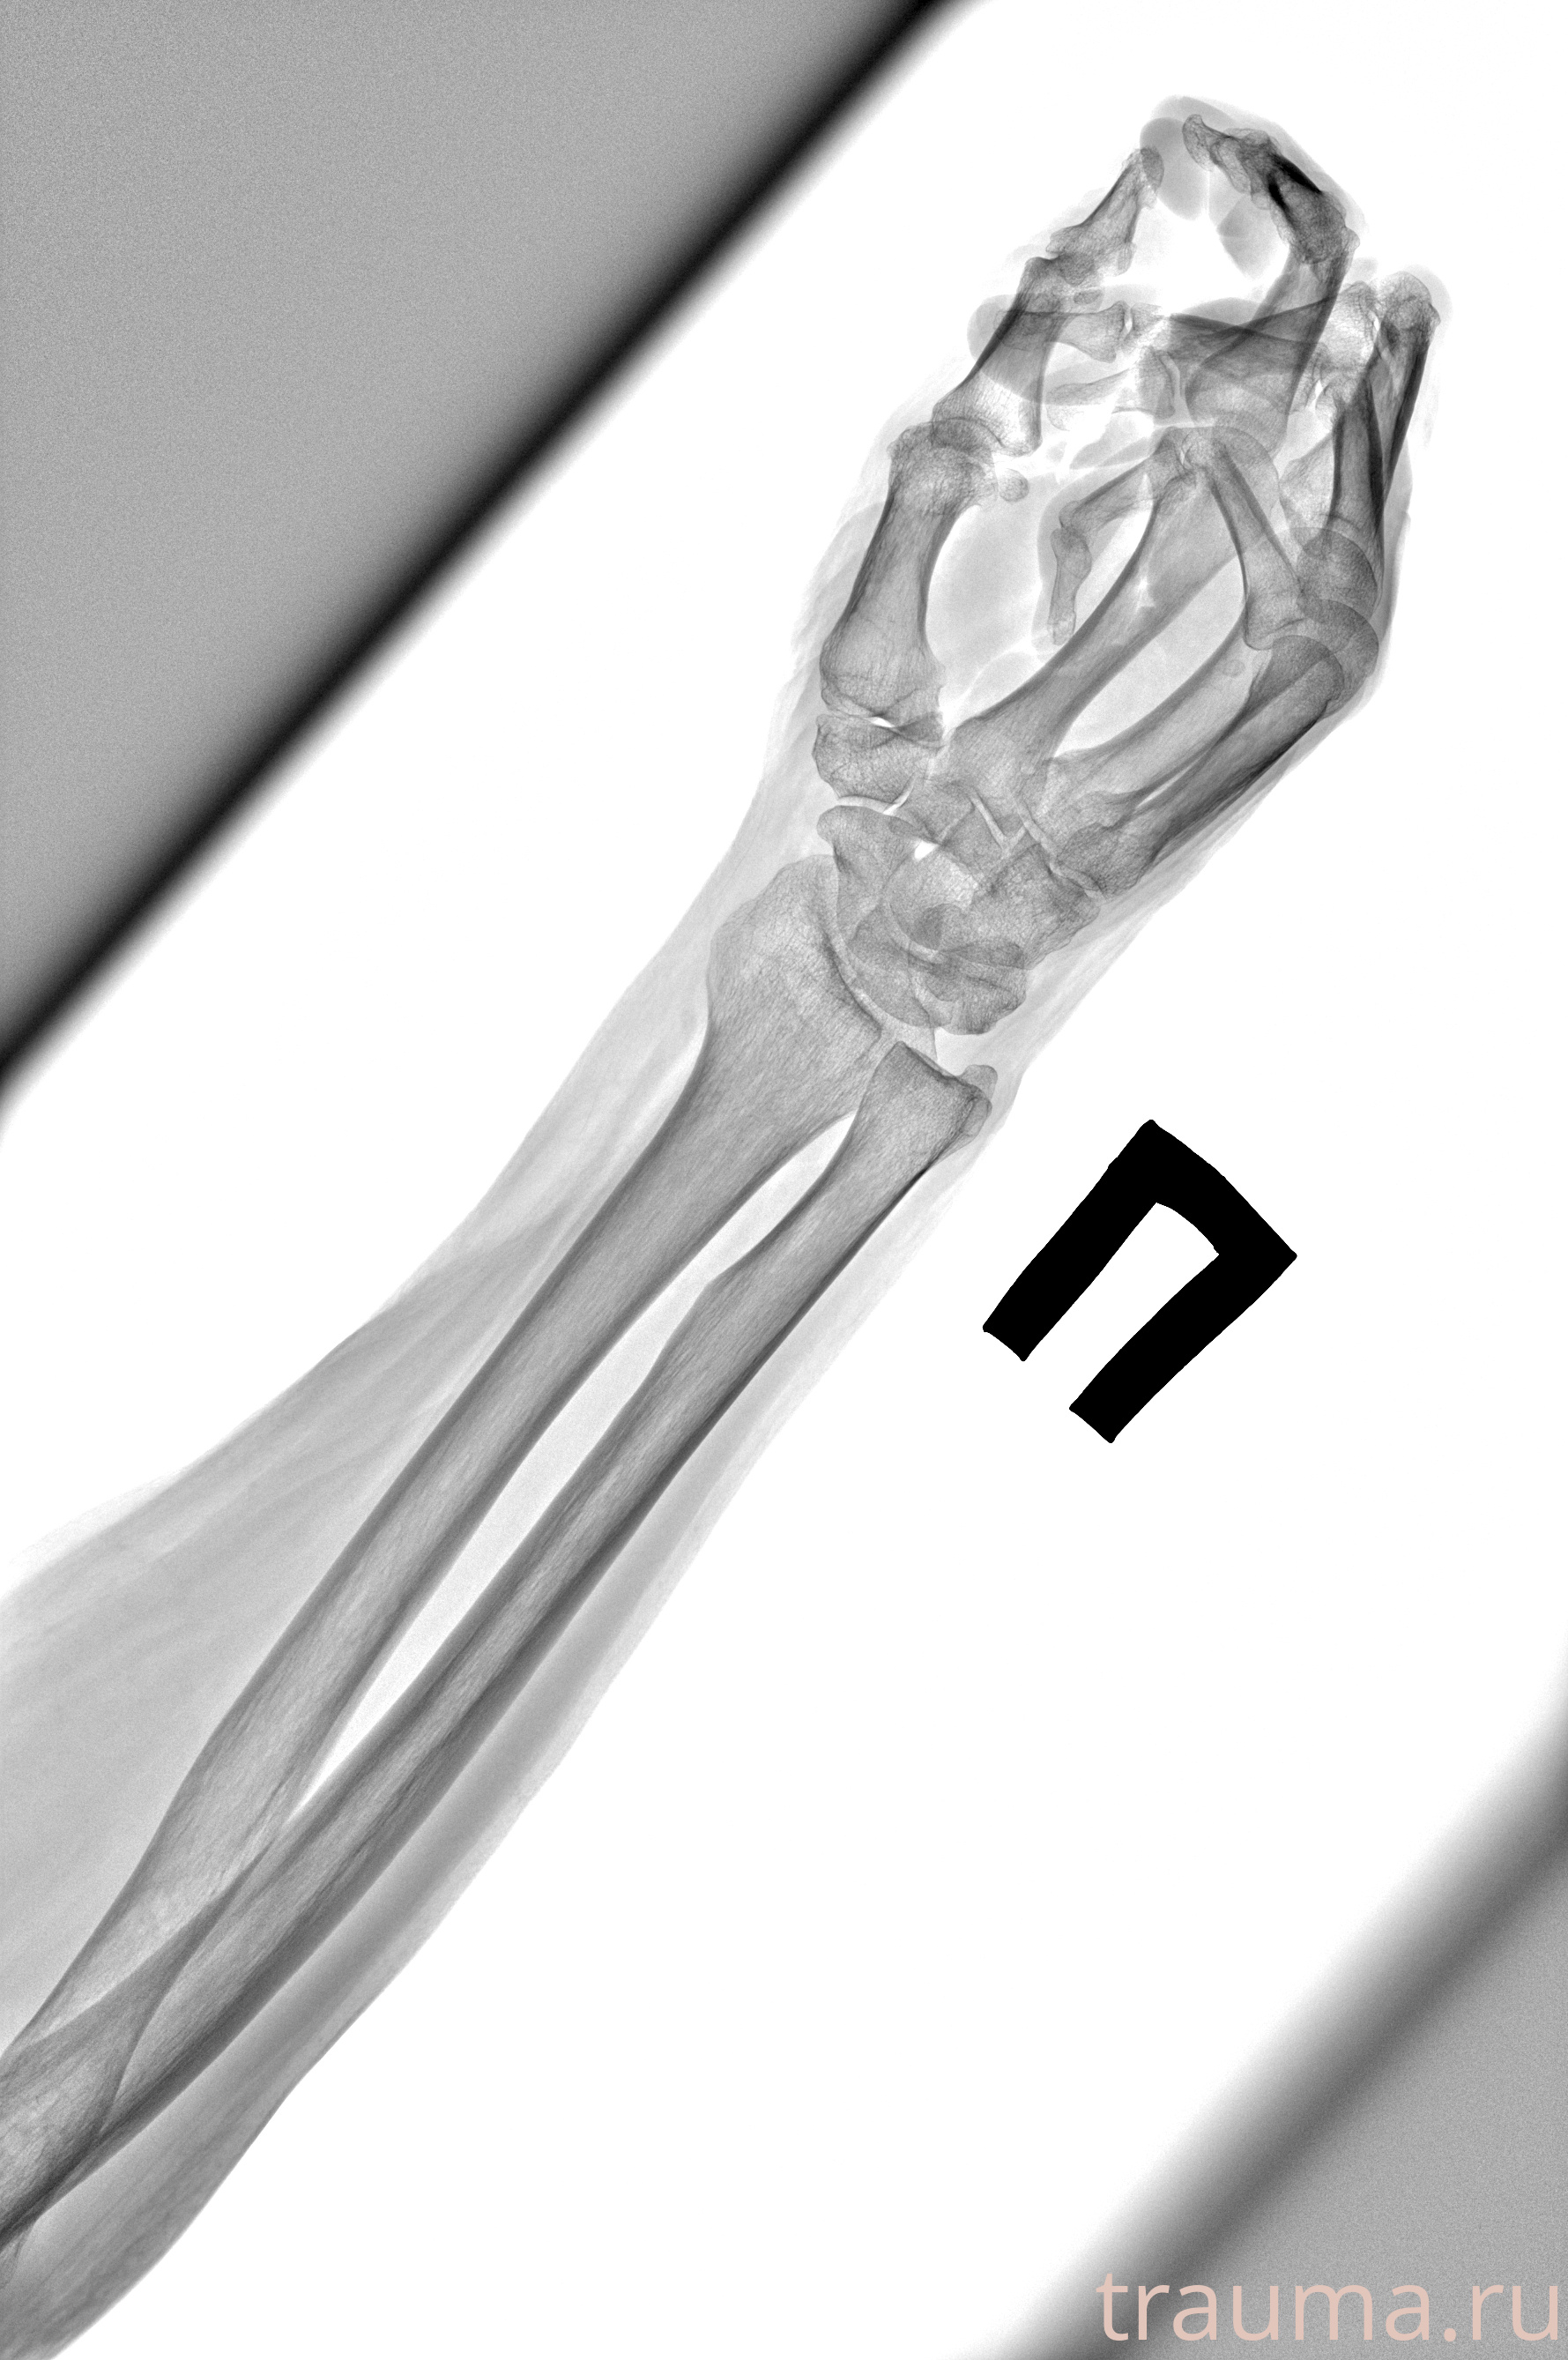

Рентген на дому: по вашему адресу приезжает врач-рентгенолог, травматолог-ортопед с мобильным рентгеновским аппаратом, проводит диагностику травмы или заболевания, делает необходимые рентгенограммы, дает рекомендации по дальнейшему лечению. Получить качественные снимки в домашних условиях возможно благодаря уникальной методике, разработанной МосРентген Центром для института  Склифосовского